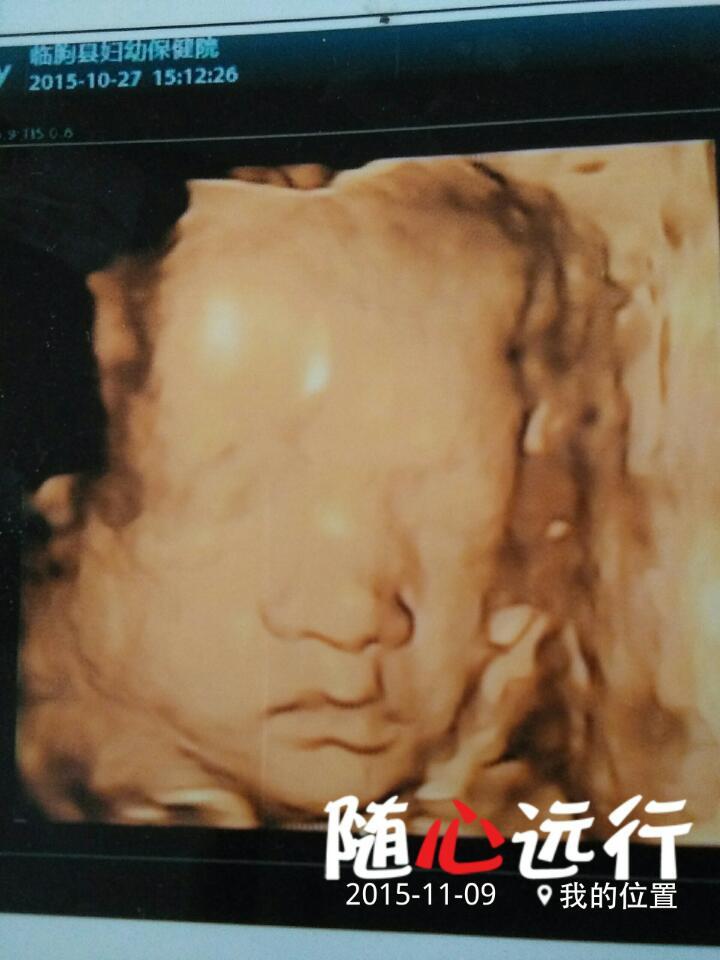

四维彩超图片,宝宝不是兔唇吧,医生什么也没说怎么自己越看越觉得不对劲呢? 四维彩超图片,宝宝不是兔唇吧,医生什么也没说怎么自己越看越觉得不对劲呢? 点击展开 朵宝 2015-11-15 23:52 为您推荐: 其他回答 这样医生也太不负责了吧,怎么会什么也没说,这也太明显了,宝妈怎么做呢? 159*****981_j1DQ 2015-11-16 00:29 相关问题 怀孕六个月昨天做四维彩超检查觉得宝宝的嘴好像不对劲 谁懂这个能帮我看看吗不会是兔唇吧 你好医生我想问一下,父母都没有缺陷,为什么生的小孩却是兔唇? 今天跟朋友聊天 朋友说 怀孕期间爱哭,爱生气,孩子会是兔唇,请问医生是真的吗?